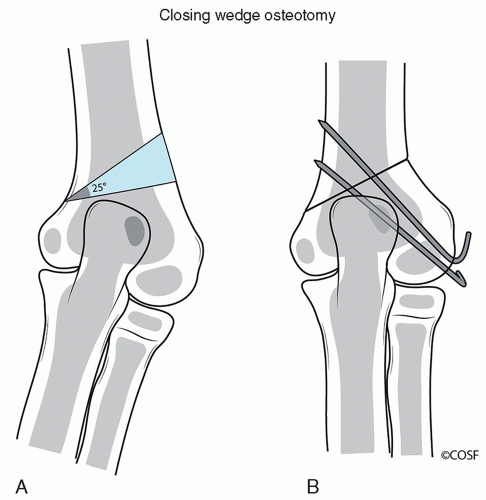

Closing wedge osteotomy (Figure 14.2)